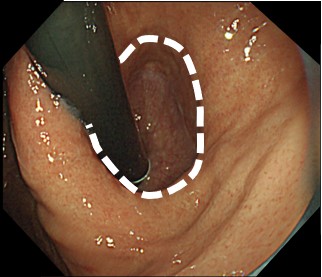

内視鏡で胃と食道のつなぎ目の粘膜を切除して、修復過程で狭くなることを利用して、逆流を防止します。